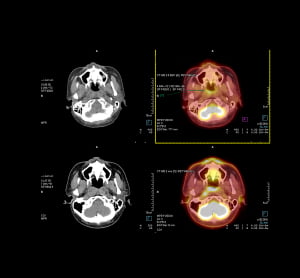

One of the biggest breakthroughs in medical imaging is the use of machine learning algorithms to help detect tumours, lesions and other abnormalities in cells.

Whilst AI has been used in many different fields, in the medical world it is used to interpret data from MRI scans or cell samples, first by being told what to look for, and then using that model on a vast amount of data.